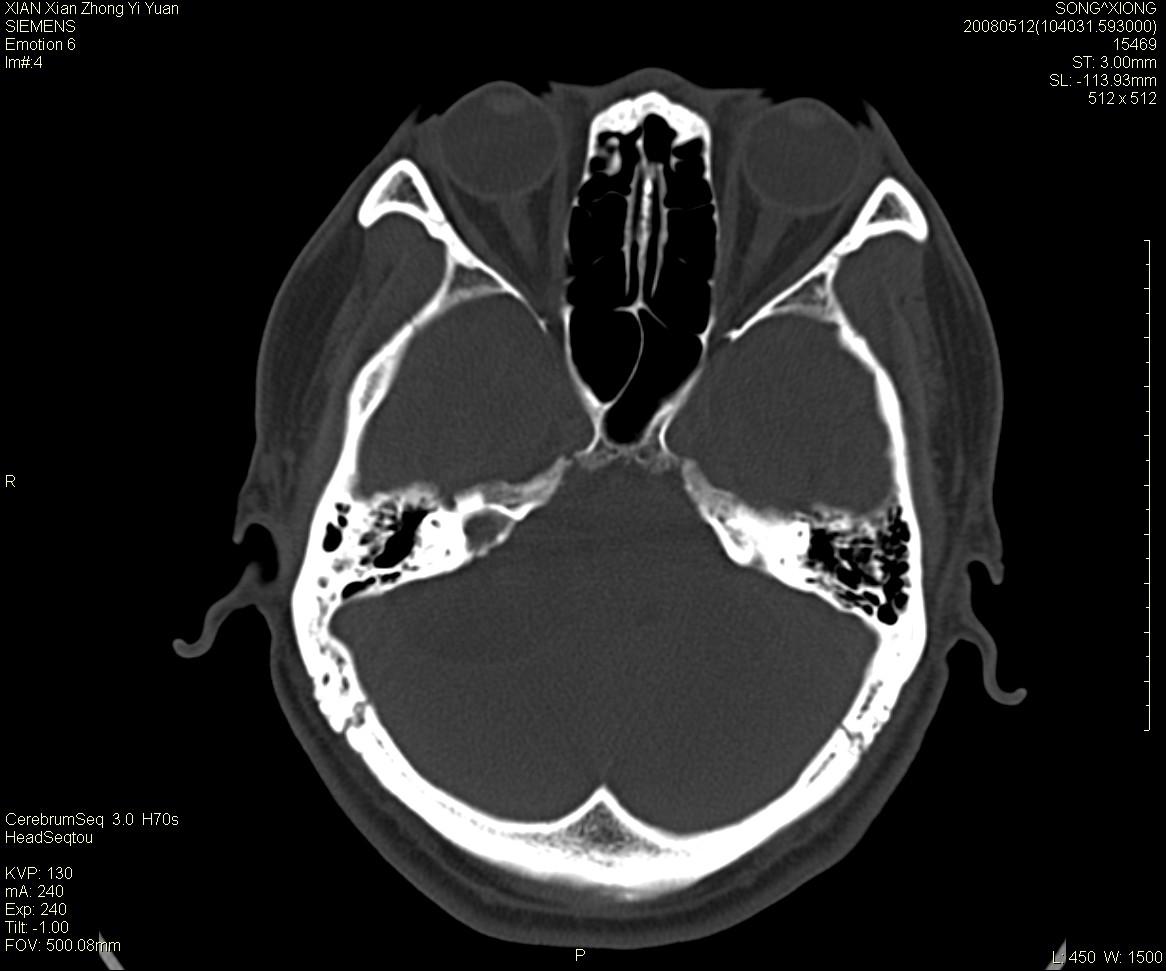

右侧内耳道慢性增宽,内耳道口出可见稍高密度影,桥小脑角池可见以较大低密度影,内缘较清,小脑、脑干、第四脑室受压、移位。

考虑:听神经瘤。

骨窗显示内听道扩大,考虑右侧听神经瘤

典型的右侧听神经瘤。